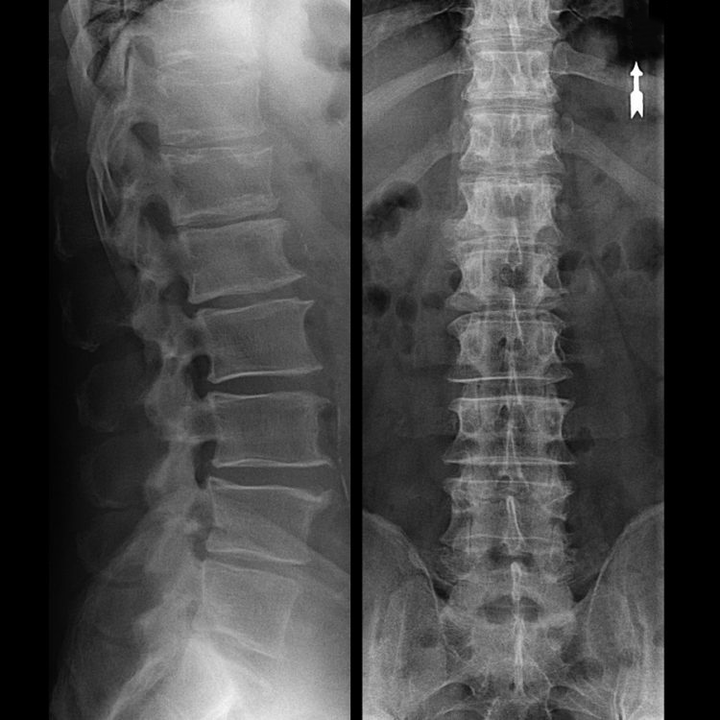

osteocondrose da região vertebral na radiografia

A “radiografia” da coluna cervical, e mesmo com testes funcionais de flexão e extensão, não mostra cartilagem, pois seu tecido transmite raios X. Apesar disso, com base na localização das vértebras, podem-se tirar conclusões gerais sobre a altura dos discos intervertebrais, o endireitamento geral da curvatura fisiológica do pescoço - lordose, bem como a presença de crescimentos marginais nas vértebras com irritação prolongada de suas superfícies por discos intervertebrais frágeis e desidratados. Testes funcionais podem confirmar o diagnóstico de instabilidade da coluna cervical.